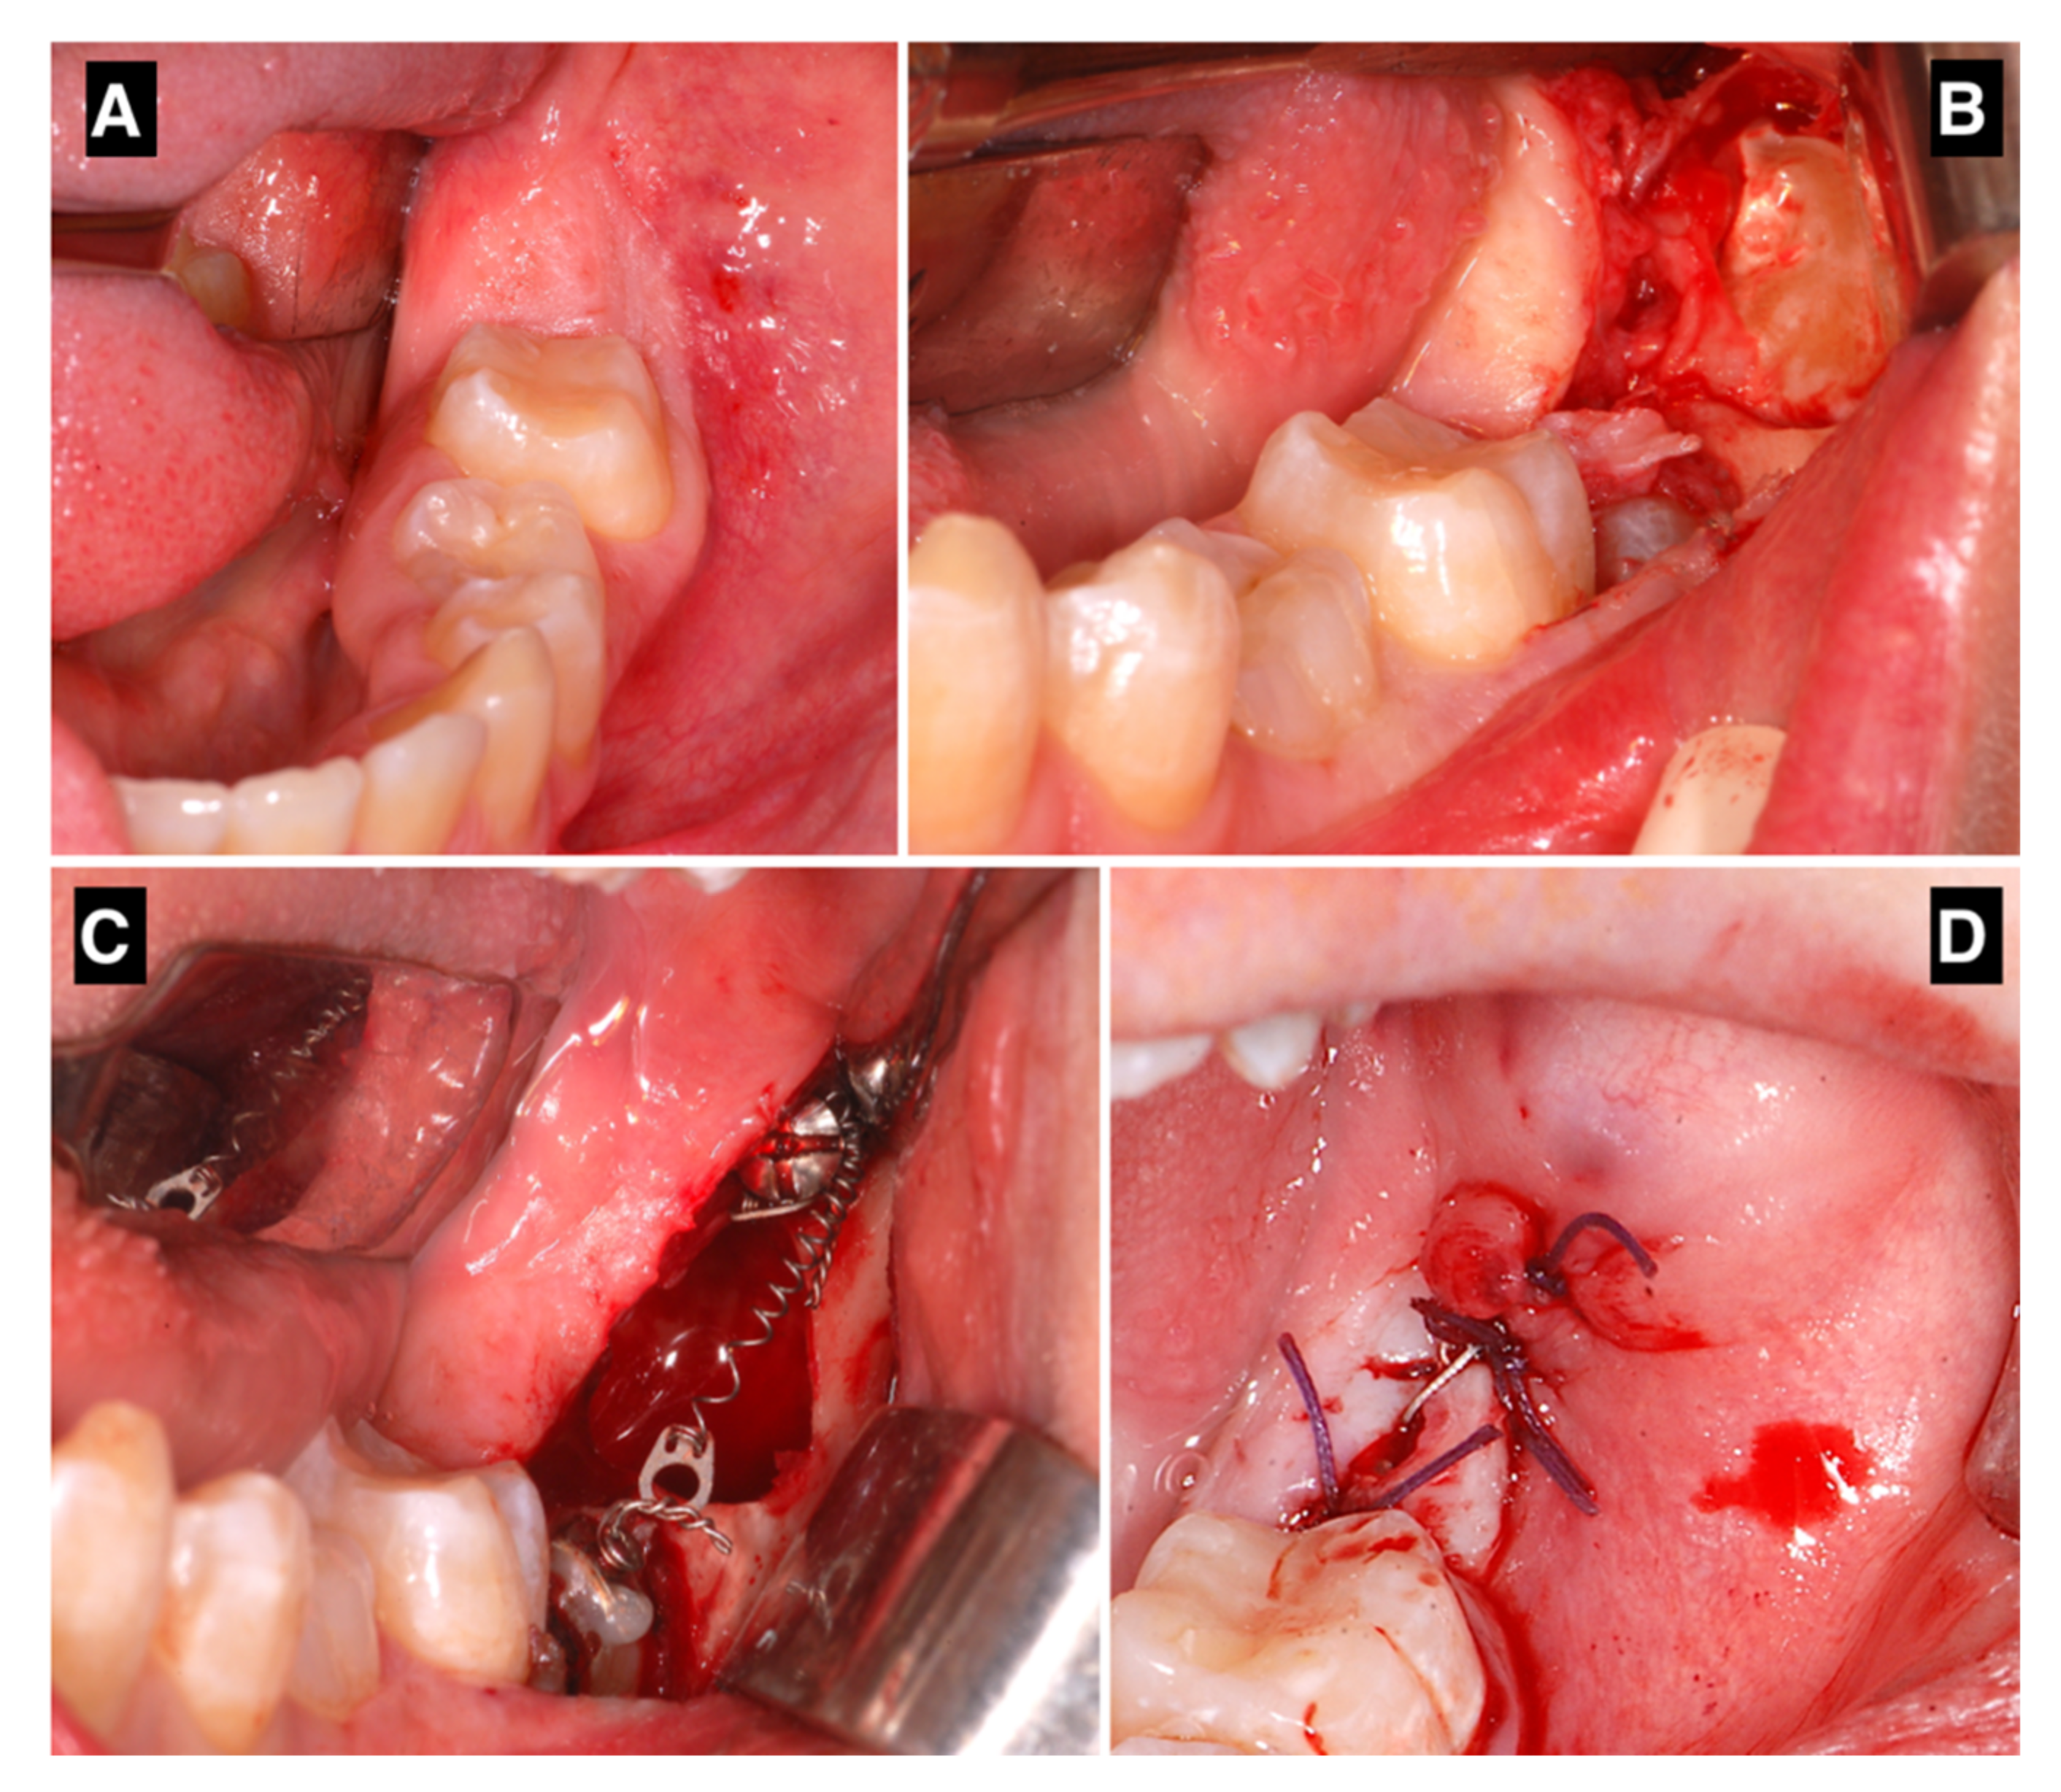

2.2. Surgical and Orthodontic Procedures

2.3. Measurements

3. Results